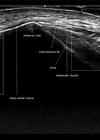

Figure 1: NSL scale.

A useful pre- and post-treatment scoring tool that assists in correct patient selection is the neck skin laxity (NSL) scale [4] (Figure 1). Patients scoring 1–3 tend to see the most effective outcomes from this treatment. Those in the more severe category scoring 4 are more likely to be a surgical candidate or may require multiple repeated sessions to obtain improvement. Patients with excessive submental fat should be excluded, as there is unlikely to any improvement for this indication.